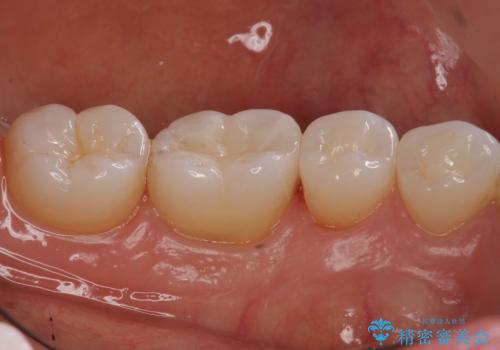

奥歯の虫歯 セラミックインレーでの治療

- 奥歯の黒ずみが気になるとのことで来院されました。

検査の結果、歯と歯の間に小さな虫歯ができていることが確認できました。

白い詰め物をご希望されたため、今回はセラミックインレーでの治療となりました。

- 右下6 セラミックインレー 77,000円費用は治療当時の料金となります

黒ずみもなくなり、虫歯も取り切ることができ大変満足していただけました。

虫歯の除去後に適合の良い修復物を装着することは今後の虫歯リスクを減らすことに繋がります。